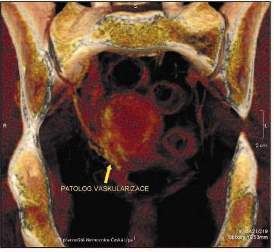

Nález na ostatních nitrobřišních orgánech byl normální. Na CT vyšetření malé pánve bylo v děložním fundu patrné kulovité nehomogenní ložisko 35 x 39 x 43 mm s patologickou vaskularizací. Viz obr. č. 2. Zachycené lymfatické uzliny v malé pánvi a obou tříslech nebyly zvětšené. Skiagram hrudníku a cystouretroskopie byly bez patologického nálezu. Kolonoskopie mimo drobných, histologicky ověřených, hyperplastických polypů byla rovněž negativní. Laboratorní vyšetření byla bez významných odchylek.

Obr. č. 2

Patologická vaskularizace v metastáze maligního melanomu děložního těla.

Počítačová tomografie. Převzato se svolením CT pracoviště Nemocnice Česká Lípa.